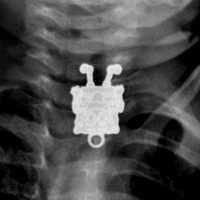

Axiom Mobile Imaging had a successful exit. We are no longer in business. Axiom did portable x-rays, ultrasounds and cardiac echoes for nursing home residents, homebound patients and even busy professionals to achieve higher quality patient care and better outcomes at a lower cost with ultimate convenience. Diagnostic Laboratories and Radiology is currently serving the customers previously served by Axiom. To order exams: 800-660-0531 Fax #: 818-333-7198 More info at: www.diaglabs.com